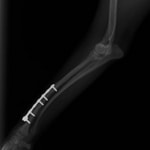

脛骨骨折 : 症例1 | 症例2 | 症例3 | 症例4 | 症例5

当院ではAdvanced Locking plate system(ALPS)と、Locking compression plate system(LCPS)という骨接合法で骨折症例の治療を行っています。

LCPは、スクリュー(ネジ)とプレート(金属の板)をロックする特殊な構造により骨折部位を固定する新しい世代のプレートシステムです。ひとつのホールでロッキングスクリューとスタンダードスクリューの使用を選択できるユニークな構造をしているため、骨折断端間の圧迫を目的とした従来型プレート固定法に加え、高い角度安定性を有するロッキングスクリューを用いた固定法の選択が可能です。従来のプレートシステムでは困難だった部分の骨折や癒合不全の症例に高い治療効果をもたらします。